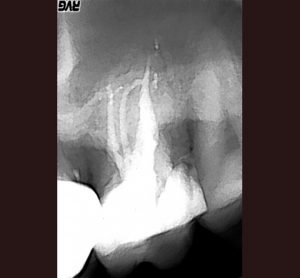

AllAccess Design and ClosureApexificationCBCT DiagnosisCracked TeethCrown Build-upEndodontic MicrosurgeryEndodontic RetreatmentEndodonticsImplantsInternal BleachingMB RootResorption Repair Endodontic Treatment: Case #1- Patient referred due to pain after recent crown cementation. Endodontic Treatment: Case #2 -Patient referred due to pain in her upper first pre molar tooth # 4 Endodontic Treatment: Case #3 – Patient referred due to pain to biting. The amalgam filling was done many years ago. Endodontic Treatment: Case #4 – Patient presented for root canal therapy referred to our office due to complex root anatomy. Endodontic Treatment: Case #5 – Necrotic (dead nerve) tooth with biting pain. Endodontic Treatment: Case #6- Necrotic (dead nerve) tooth with no pain referred for treatment. Endodontic Treatment: Case #7- Very unique tooth with lots of canals (this was a dentists tooth!) Endodontic Treatment: Case #8 – recently prepared for a crown. The patient has cold sensitivity and was referred for treatment. Endodontic Treatment: Case #9- Interesting root anatomy and diagnosis. Endodontic Treatment: Case #10 – 4 canalled lower first molar with 2 distals and 2 mesial canals with a common apex of the mesial root system. Endodontic Treatment: Case #11 Endodontic Treatment: Case #12- Four canalled lower first molar. Finding MB2 The MB Root: Case # 1 The MB Root: Case #2 The MB Root: Case #3 The MB Root: Case #4 The MB Root: Case #5 The MB Root: Case #6 The MB Root: Case #7 The MB Root: Case #8 The MB Root: Case #9 Maxillary MB Root: 1 Mandibular MB Root: 1 Mandibular MB Root: 2 Maxillary MB Root: 2 Mandibular MB Root: 3 Maxillary MB Root: 3 Mandibular MB Root: 4 Endodontic Retreatment: Case #1 – Silver point root canal that was performed 30 years earlier. Endodontic Retreatment: Case #2- Retreatment of initial root canal done 15 years earlier. Endodontic Retreatment: Case #3- Retreatment of a recent root canal performed 2 weeks earlier. Endodontic Retreatment: Case #4 – Retreatment of initial root canal done 12 years earlier Endodontic Retreatment: Case #5 – Retreatment of initial root canal done 30 years earlier. Endodontic Microsurgery: Case #1 Endodontic Microsurgery: Case #2 Endodontic Microsurgery: Case #3 Endodontic Microsurgery: Case #4 Endodontic Microsurgery: Case #5 – Intentional replantation (not so common procedure) Access Closure: Case #1 Access Closure: Case #2 Access Closure: Case #3 Access Closure: Case #4 Access Closure: Case #5 Access Closure: Case #6 Access Closure: Case #7 Access Closure: Case #8 Access Closure: Case #9 Access Closure: Case #10 Access Closure: Case #11 Crown Build-up: Case #1 Crown Build-up: Case #2 Crown Build-up: Case #3 – with bicuspid teeth they are more prone to fracture. Crown Build-up: Case #4 – with bicuspid teeth they are more prone to fracture. Crown Build-up: Case #5 Crown Build-up Case #6 Cracked Teeth: Case #1 Cracked Teeth: Case #2 Cracked Teeth: Case #3 Cracked Teeth: Case #4 Cracked Teeth: Case #5 Cracked Teeth: Case #6 Cracked Teeth: Case #7 Implants: Case #2 Implants: Case #3 Implants: Case #1 Implants: Case #10 Implants: Case #9 Implants: Case #8 Implants: Case #7 Implants: Case #6 Implants: Case #5 Implants: Case #4 CBCT Diagnosis: Case #12 CBCT Diagnosis: Case #11 CBCT Diagnosis: Case #10 CBCT Diagnosis: Case #9 CBCT Diagnosis: Case #8 CBCT Diagnosis: Case #7 CBCT Diagnosis: Case #6 CBCT Diagnosis: Case #5 CBCT Diagnosis: Case #4 CBCT Diagnosis: Case #3 CBCT Diagnosis: Case #2 CBCT Diagnosis: Case #1 High Magnification of Resorption Resorption Repair: Case #5 Resorption Repair: Case #4 Resorption Repair: Case #3 Resorption Repair: Case #2 Resorption Repair: Case #1 Internal Bleaching: Case #3 Internal Bleaching: Case #2 Internal Bleaching: Case #1 Apexification of Lower Premolar